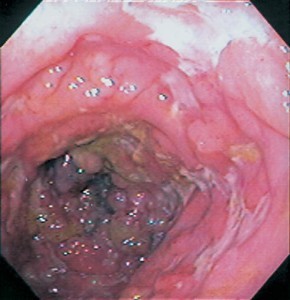

A 55 year old obese man reports frequent chest pain, especially after eating spicy foods or drinking coffee. What is his diagnosis based on the endoscopic exam and what are the complications of this condition?

GERD: see hyperemia, vertical linear streaks due to mucosal erosions/ulcers

Pathogenesis:

Associated symptoms: Regurgitation, pulmonary symptoms (adult-onset asthma), cough (at night), hoarseness, laryngitis, chest pain, disturbed sleep

Lab tests:

1) 24-hour ambulatory esophageal pH monitoring= gold standard (measures proximal and distal esophagus, stomach pH)

2) Endoscopy (with biopsy)- rule out other pathology, look for Barrett’s

3) Bernstein test= reproduce patient’s symptoms by infusing acid into esophagus

Complications: Esophagitis–> peptic stricture, esophageal hemorrhage, ulcer, pulmonary symptoms, Barrett’s esophagus